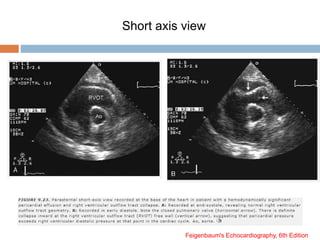

 RV Diastolic Collapse

 Most commonly involves the RV outflow tract (more

compressible area of RV)

 Occurs in early diastole, immediately after closure of the

pulmonary valve, at the time of opening of the tricuspid valve

 When collapse extends form outflow tract to the body of the right

ventricle, this is evidence that intrapericardial pressure is

elevated more substantially

Short axis view

Feigenbaum's Echocardiography, 6th Edition